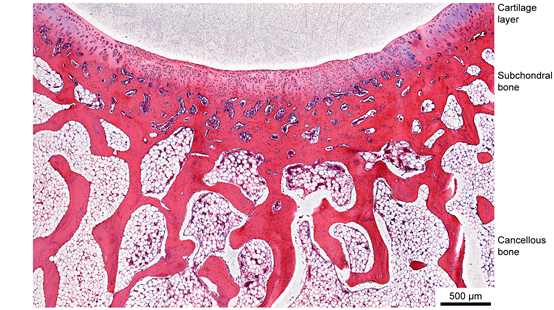

图3 再生关节软骨及其周边的组织学显微图片